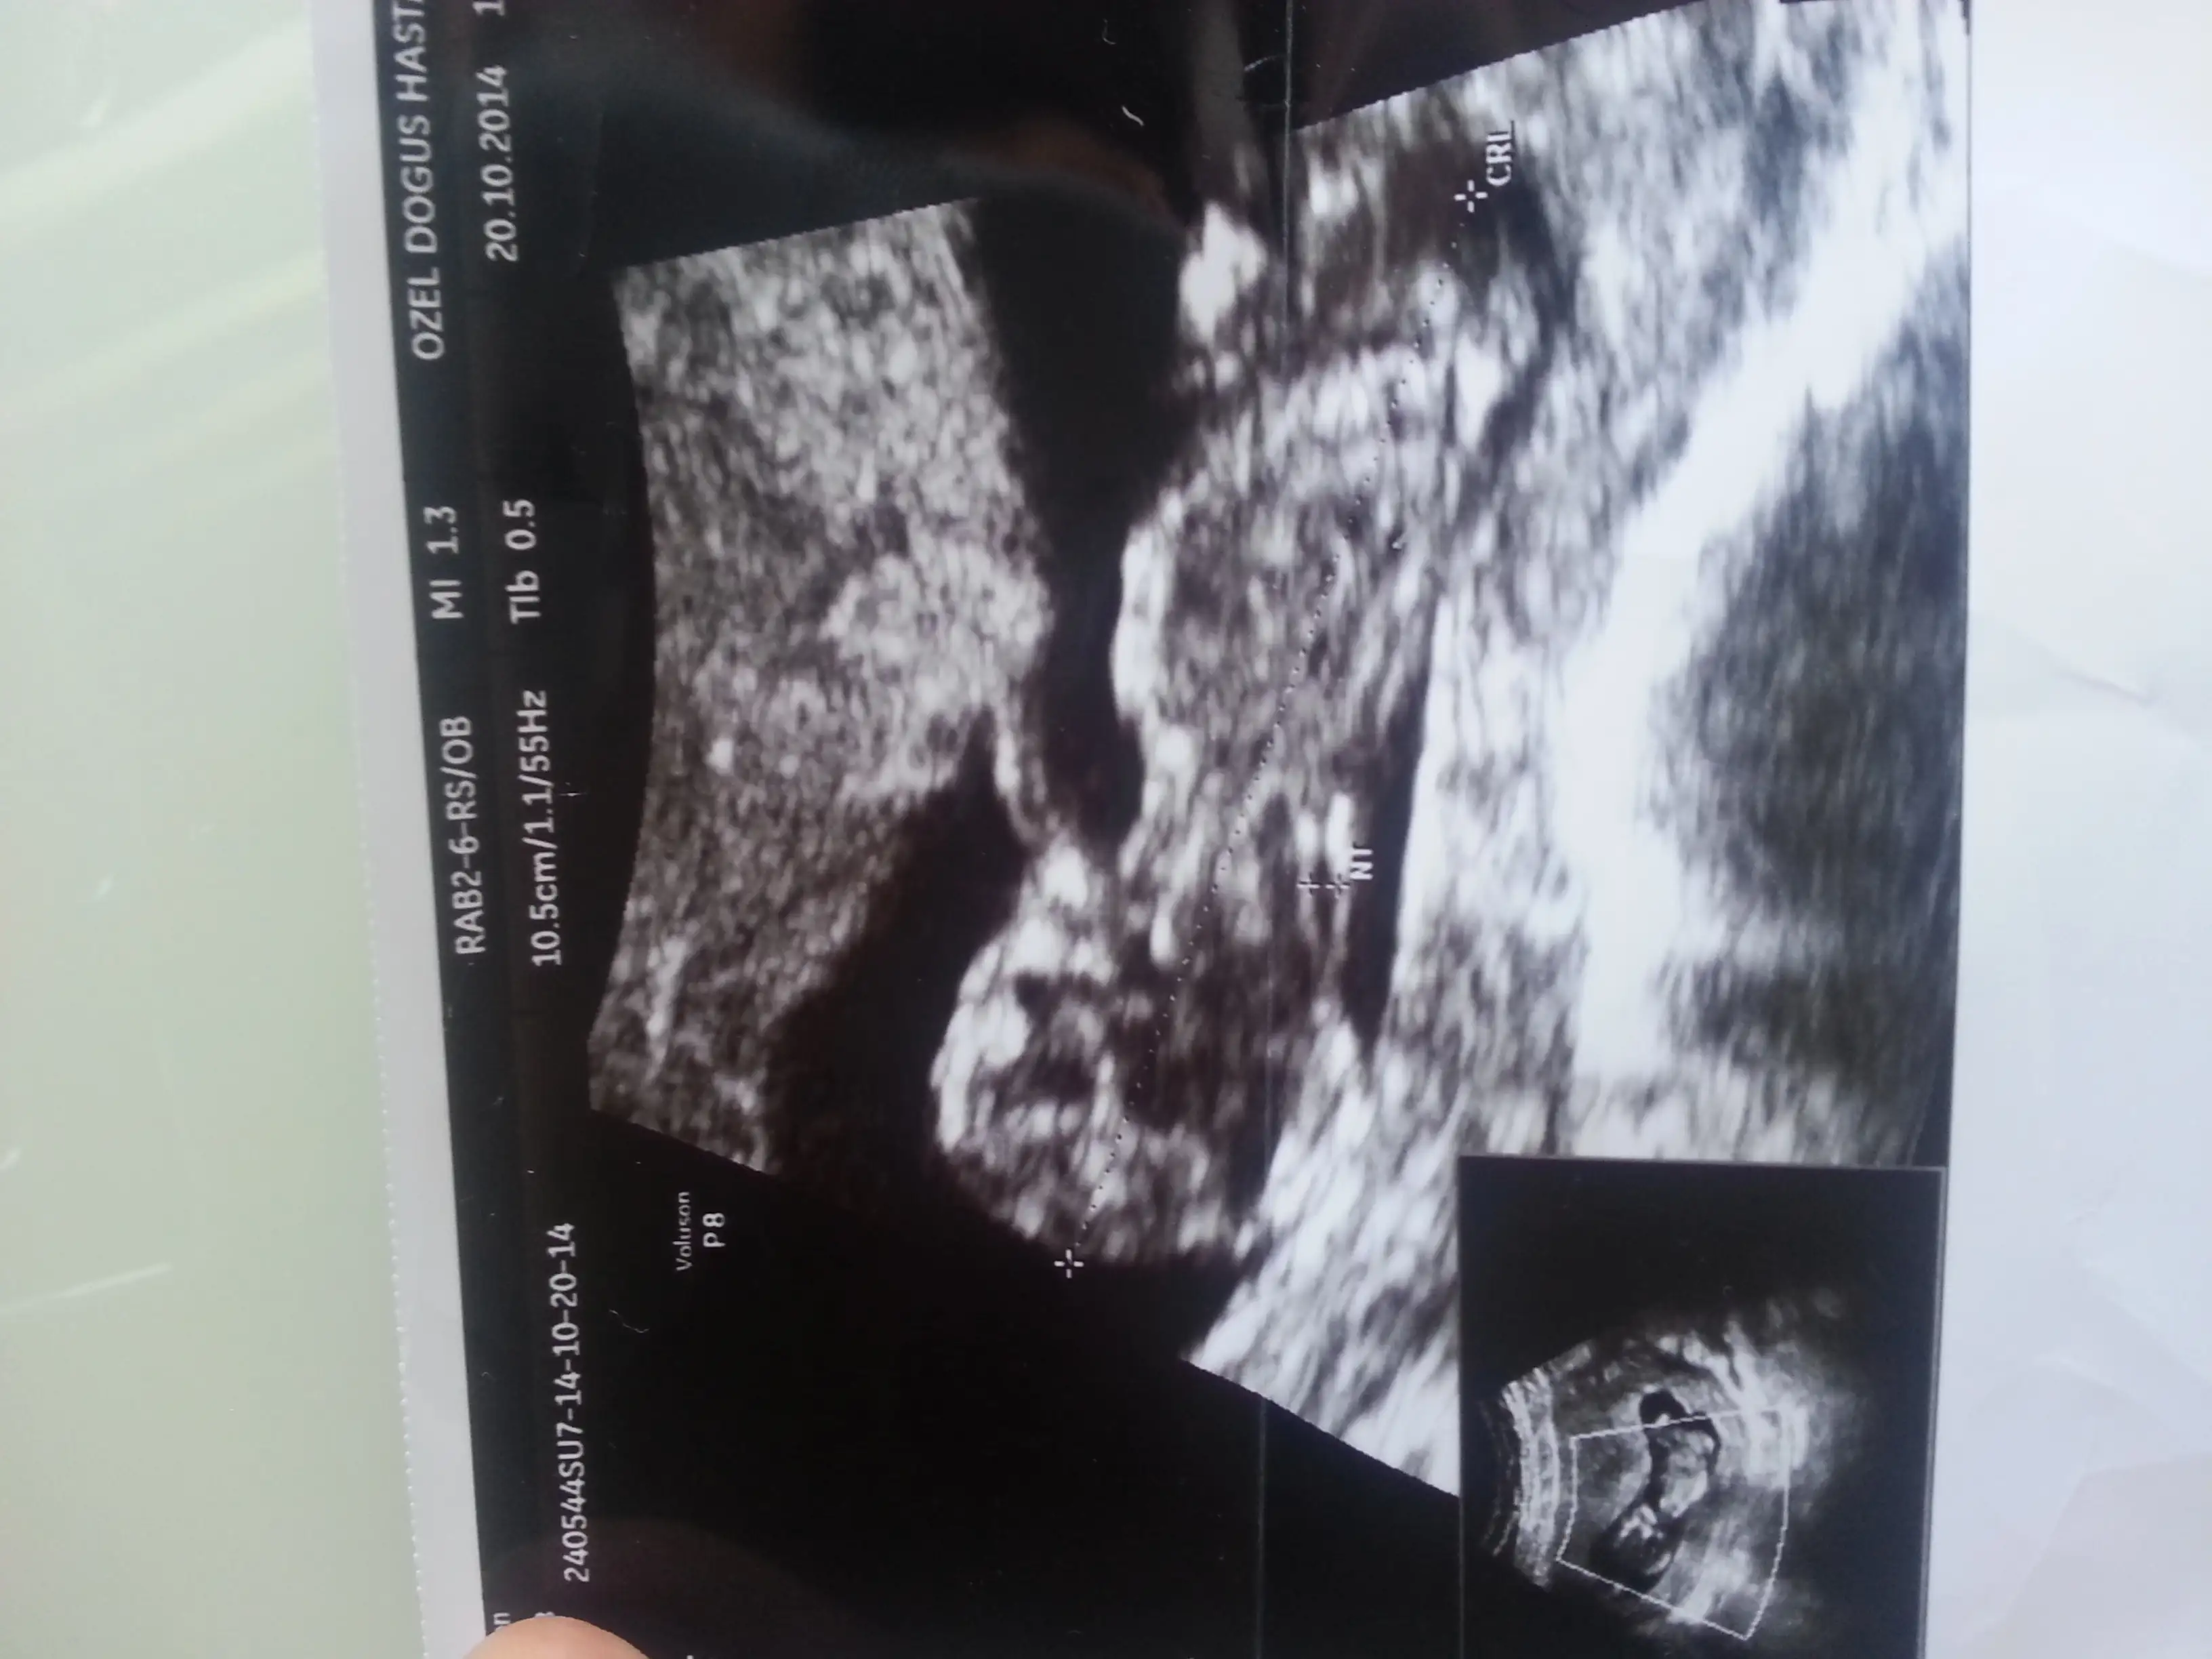

Kızlar neden kimse bana yorum yapmıyor nolur bide benim fotolara bakınboy ölçüm çizgisinin popo kısmından biraz yukarıda dik bir şey var gibi ama arkası dönük olduğu için kesin diyemiyorum.

Hiç görünmüyor canmBenimkine de yorum yapar mısın lütfen

Size yorum yaptimmi bilmiyorum ama kız olabilir bebisiniz bazı arkafaslarinki gorunmuyo resimleri telden giriyorum oyuzden acmiyo fotolarKizlar benim onceki gonderime sagolsun hcan86 arkadas yorum yapti ama bu isi anlayabilen diger arkadaslarda yorum yapabilirler mi acaba?

Elimde bu pozisyonla ilgili baska bi foto yok malesef nub cikintisi popoya paralel mi geldi sizeSana